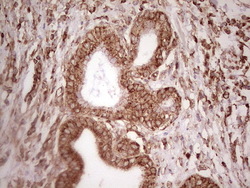

- Main image

- Experimental details

- Immunohistochemical staining of paraffin-embedded Human prostate tissue within the normal limits using anti-WIBG mouse monoclonal antibody. (Heat-induced epitope retrieval by 1 mM EDTA in 10mM Tris, pH8.5, 120C for 3min, TA806496)

- Validation comment